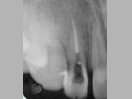

After 2 years

x-ray post operation